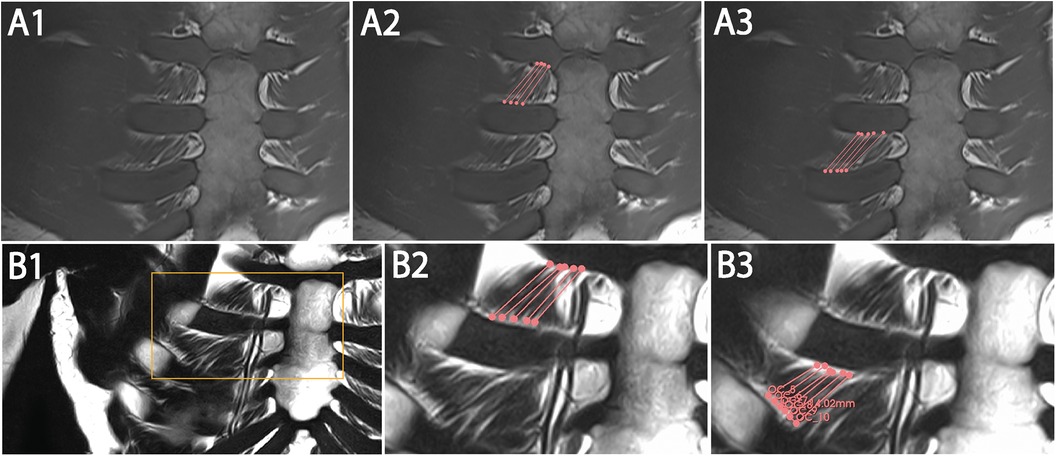

Interfascicular distance based on T2W coronal and para-axial sequences

The distance between five adjacent fascicles (I–V, Table 7) of internal ICM in ICS 2 and 3 was quantified. Exemplary annotation and 3D Slicer analysis are shown in Figure 4, following the approach of Figure 3. Quantified coronal interfascicular distance of 15 measured fascicles in each ICS showed a smaller mean value in ICS 2 (3.00 ± 0.30 mm) compared with ICS 3 (3.21 ± 0.68 mm). However, para-axial interfascicular distance demonstrated in ICS 2 (3.47 ± 0.71 mm) and ICS 3 (3.41 ± 0.60 mm) higher values compared with coronal assessment and demonstrated a higher overall mean value of 3.44 mm and a higher intersubject SD of 0.66. Comparing coronal and para-axial approach value differences were not significant (ICS 2, p = 0.1256; ICS 3, p = 0.6087). The summed interfascicular distance of internal ICM values in ICS 2 (3.11 ± 0.54 mm) and ICS 3 (3.44 ± 0.67 mm) showed comparable mean values.

Figure 4

MRI scans and measurements in images A1-A3 and B1-B3, tracking interfascicular distances within a structure, illustrated by marked lines and data points. Bar graph C shows interfascicular distance measurements for ICS 2 and ICS 3, with specific values of 0.1256 and 0.6087 millimeters.

Figure 4. Representative T2W MRI images with coronal (A1–A3) and para-axial view (B1–B3) for interfascicular distance measurement in ICS 3 with statistical analysis based on coronal and para-axial sequences of ICS 2 and ICS 3 (C). (A1) Original image of coronal T2W. (A2) Segmented internal ICM fascicles with insertion points (dots) and marked course (lines) of ICS3. (A3) Marked fascicles (dots) of A2 with indicated para-axial plane (green line) corresponding to (B). (B1) Marked fascicles (dots) corresponding to (A3) aligned to para-axial plane (line) within the same muscle layer. (B2) Exemplary para-axial interfascicular distance measurement of two fascicles (dots) within the same muscle layer and para-axial plane (line). (B3) Exemplary para-axial interfascicular distance measurement of two fascicles (dots) within the same muscle layer. (C) Analysis of mean values of T2W images derived from interfascicular distance measurement based on coronal (rectangles, white columns) and para-axial (dots, gray columns) planes in ICS 2 and ICS 3 with SEM (lines).